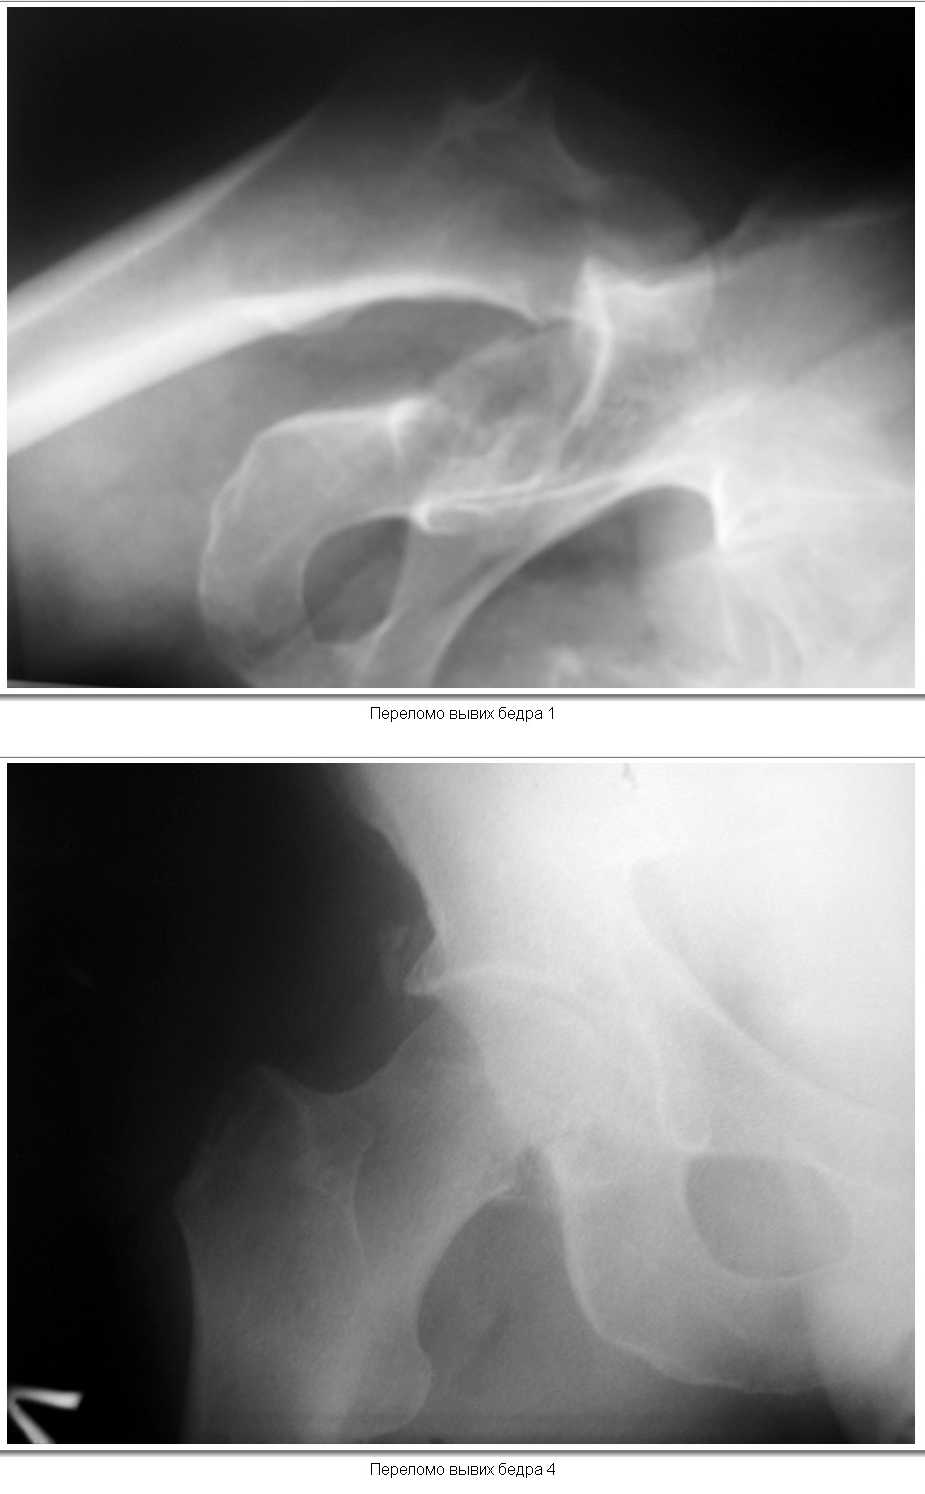

12.02.2008г.поступил пациент,мужчина ,50 лет.В результате удара бревном

получил закрытый  вывих левого бедра и переломом нижнего фрагмента

головки( тип 1 по Pipkin).При поступлении вывих вправлен,налажено

скелетное вытяжение за н\3 бедра.На контрольной рентгенограмме фрагмент

головки располагается вне полости сустава,в подвздошной области.Хотелось

бы узнать ваше мнение о необходимости оперативного лечения(Фиксации

перелома головки)и его технических особенностей(способ фиксации).КТ

выполнить  временно невозможно( поломка аппарата).